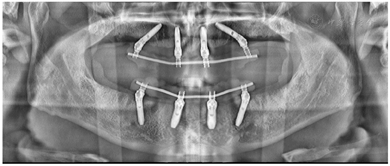

治疗过程(1)手术方案设计:拔除余留牙后,上颌拟在12、22植入2颗轴向植体,15、25植入2颗倾斜植体,下颌于32、42植入2颗轴向植体,35、45区域植入2颗倾斜植体,种植体倾斜角度小于45°,术后制作临时种植固定义齿,6月后戴终义齿(钛支架加丙烯酸树脂材料)。(2)种植一期术前测量垂直距离。术中拔除上下颌余留牙,分别于16-26、36-46区牙槽嵴顶近远中向切开牙龈黏膜,翻瓣,搔刮拔牙窝内炎性肉芽组织,平整牙槽嵴顶骨嵴,分别于12、15、22、25、32、35、42、45区定点,逐级备洞,12、22、32、42区轴向植入Nobel Speedy 4x13mm种植体,15、25、35、45区远中倾斜植入Nobel Speedy 4x15mm种植体。初期稳定性均达到35N·CM。15、25放置RP 5 mm 30°复合基台,12、22放置RP 3 mm 17°复合基台。32、42放置RP 2 mm 0°复合基台,35、45放置RP 4mm 30°复合基台,放置愈合帽,修整牙龈黏膜,缝合牙龈(图4)。术后拍摄全景片(图5)(3)即刻负重制取上下颌印模,制作蜡堤记录上下颌颌位关系,采用息止颌位法确定垂直距离,吞咽咬合法确定水平关系,转移颌位关系后,手术当日制作临时固定义齿修复至第二前磨牙并戴入固定,调整咬合接触(图6)。